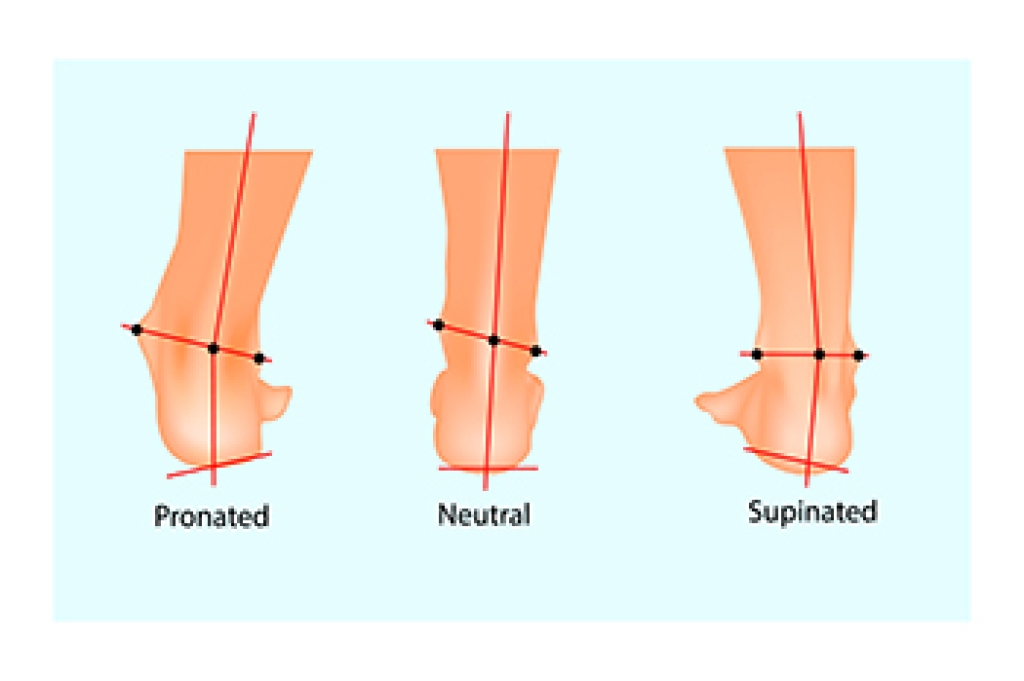

Arthritis in the feet is a condition that can bring a range of discomforts and unique sensations. It often manifests as pain and stiffness in the joints, making every step a potential challenge. Individuals with foot arthritis may experience a deep, aching pain that worsens with movement. This discomfort can be present in various areas of the foot, including the toes, the midfoot, or the ankle. One common sensation associated with foot arthritis is a feeling of stiffness or inflexibility. It can be particularly pronounced in the morning or after periods of inactivity. As arthritis progresses, swelling and warmth may accompany the pain, making the affected foot feel tender to the touch. In more advanced cases, individuals may notice a grinding or popping sensation in the affected joints, indicating the wear and tear of the cartilage. Understanding what arthritis in the feet feels like is essential for timely diagnosis and effective management. If you have any of the above symptoms which may indicate arthritis in the feet, it is suggested that you schedule an appointment with a podiatrist who can guide you toward relief methods.

Arthritic symptoms range in severity, and they may come and go. Some symptoms stay the same for several years but could potentially get worse with time. Severe cases of arthritis can prevent its sufferers from performing daily activities and make walking difficult.